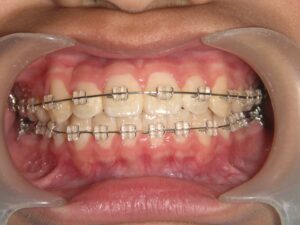

第2期治療開始時

顔貌写真

口腔内写真

開始年齢

13歳

主訴(患者様のお悩み)

残りの歯のデコボコを治したい

診断

上下顎軽度の叢生(上下の歯のデコボコ)

上顎右側犬歯低位(右上の八重歯)

治療方針

非抜歯矯正治療

全体的に装置を装着し、歯のデコボコや咬み合わせを治療

使用装置

表側矯正装置

治療期間の目安:約1年~1年半(保定期間を除いた期間)